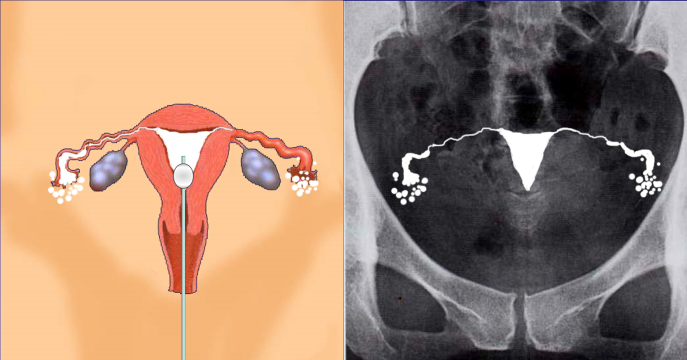

子宮卵管造影検査

妊娠をするためには卵管が通っていなければ妊娠には至りません。タイミングや排卵誘発・人工授精をしても卵管の通過性が無ければ無効であり、時間の浪費にしかなりません。通過性がなければ手術による治療か、体外受精を行わなければ妊娠に至れません。よって当院ではまずは子宮卵管造検査で卵管の通過性を確認をすることを勧めています。

通水検査等もありますが、通水検査では卵管留水症が見落とされたり、卵管の周囲の癒着の診断ができません。卵管留水症は体外受精の妊娠率を低下させます。また、油性造影剤による卵管造影検査では、検査後の妊娠率上昇も認められており、診断と妊娠率アップで良いこと2倍です。